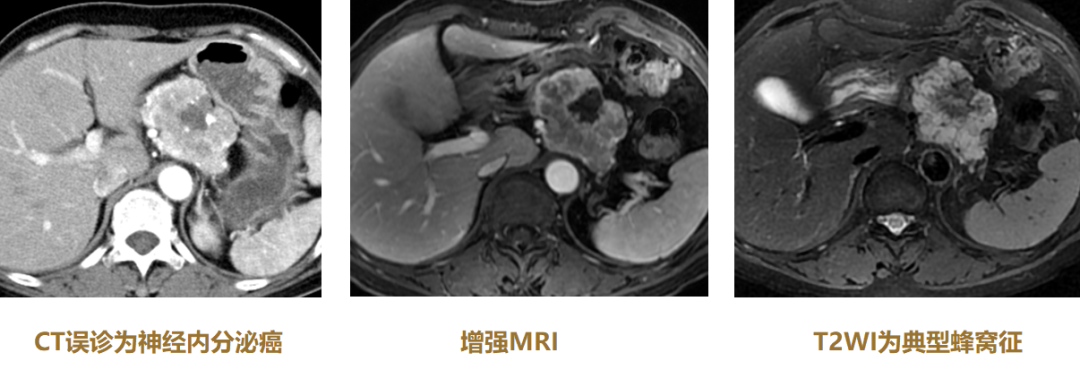

3.蜂窝征

对浆液性囊腺瘤(SCN)非常重要。微囊型SCN(全病灶蜂窝征+中心钙化+快进快出);胰腺癌-病灶内蜂窝征,必须看T2WI!

图12 微囊型SCN

(图片来源:余日胜教授讲课使用)